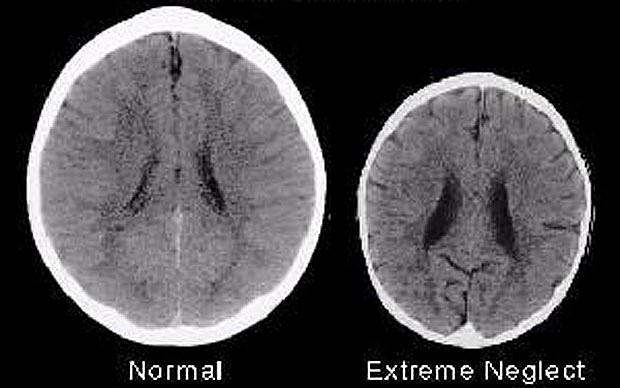

When we are born our brains are not developed to the extent they need to be to function as a social being. This “growing” happens from the moment we are born, through the interaction we receive with our carers, specifically our primary care-giver. Our brains need the love and care of a maternal, or paternal carer to connect and grow. This needs to happen from the moment we are born, or some would say the moment we are conceived.

This is what makes us go on to live our lives and determines how we function. By the age of 18 months we have learned a HUGE amount about the world and our brains have formed accordingly. If we haven’t felt love our brain literally doesn’t grow, I imagine it is a little like a flower withering. This is tragic.